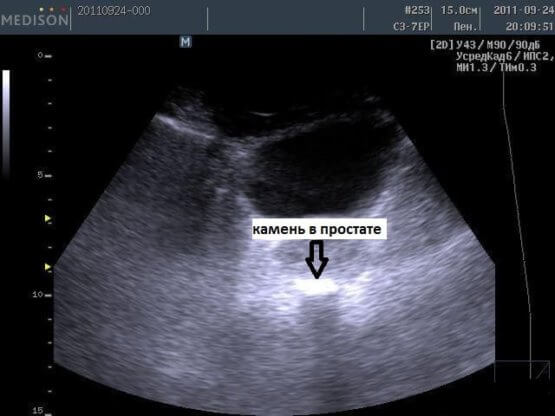

- УЗИ позволяет выявить даже мелкие камни (меньше 4 мм). При этом одновременно диагностируют застойные явления либо воспалительный процесс.